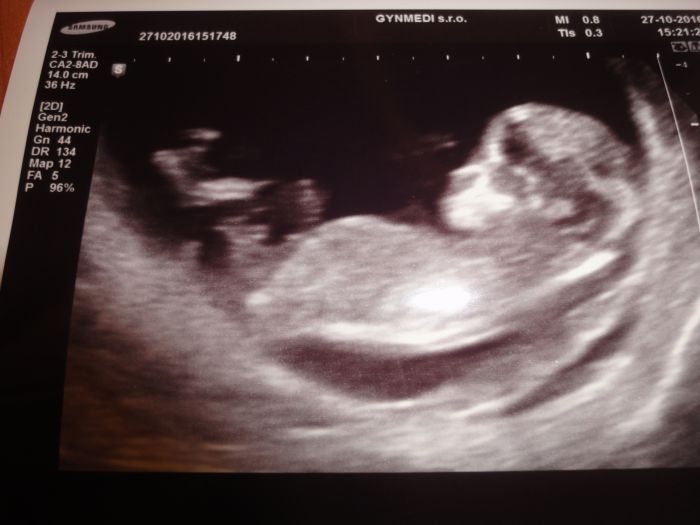

Gratuluji moc krásná fotecka